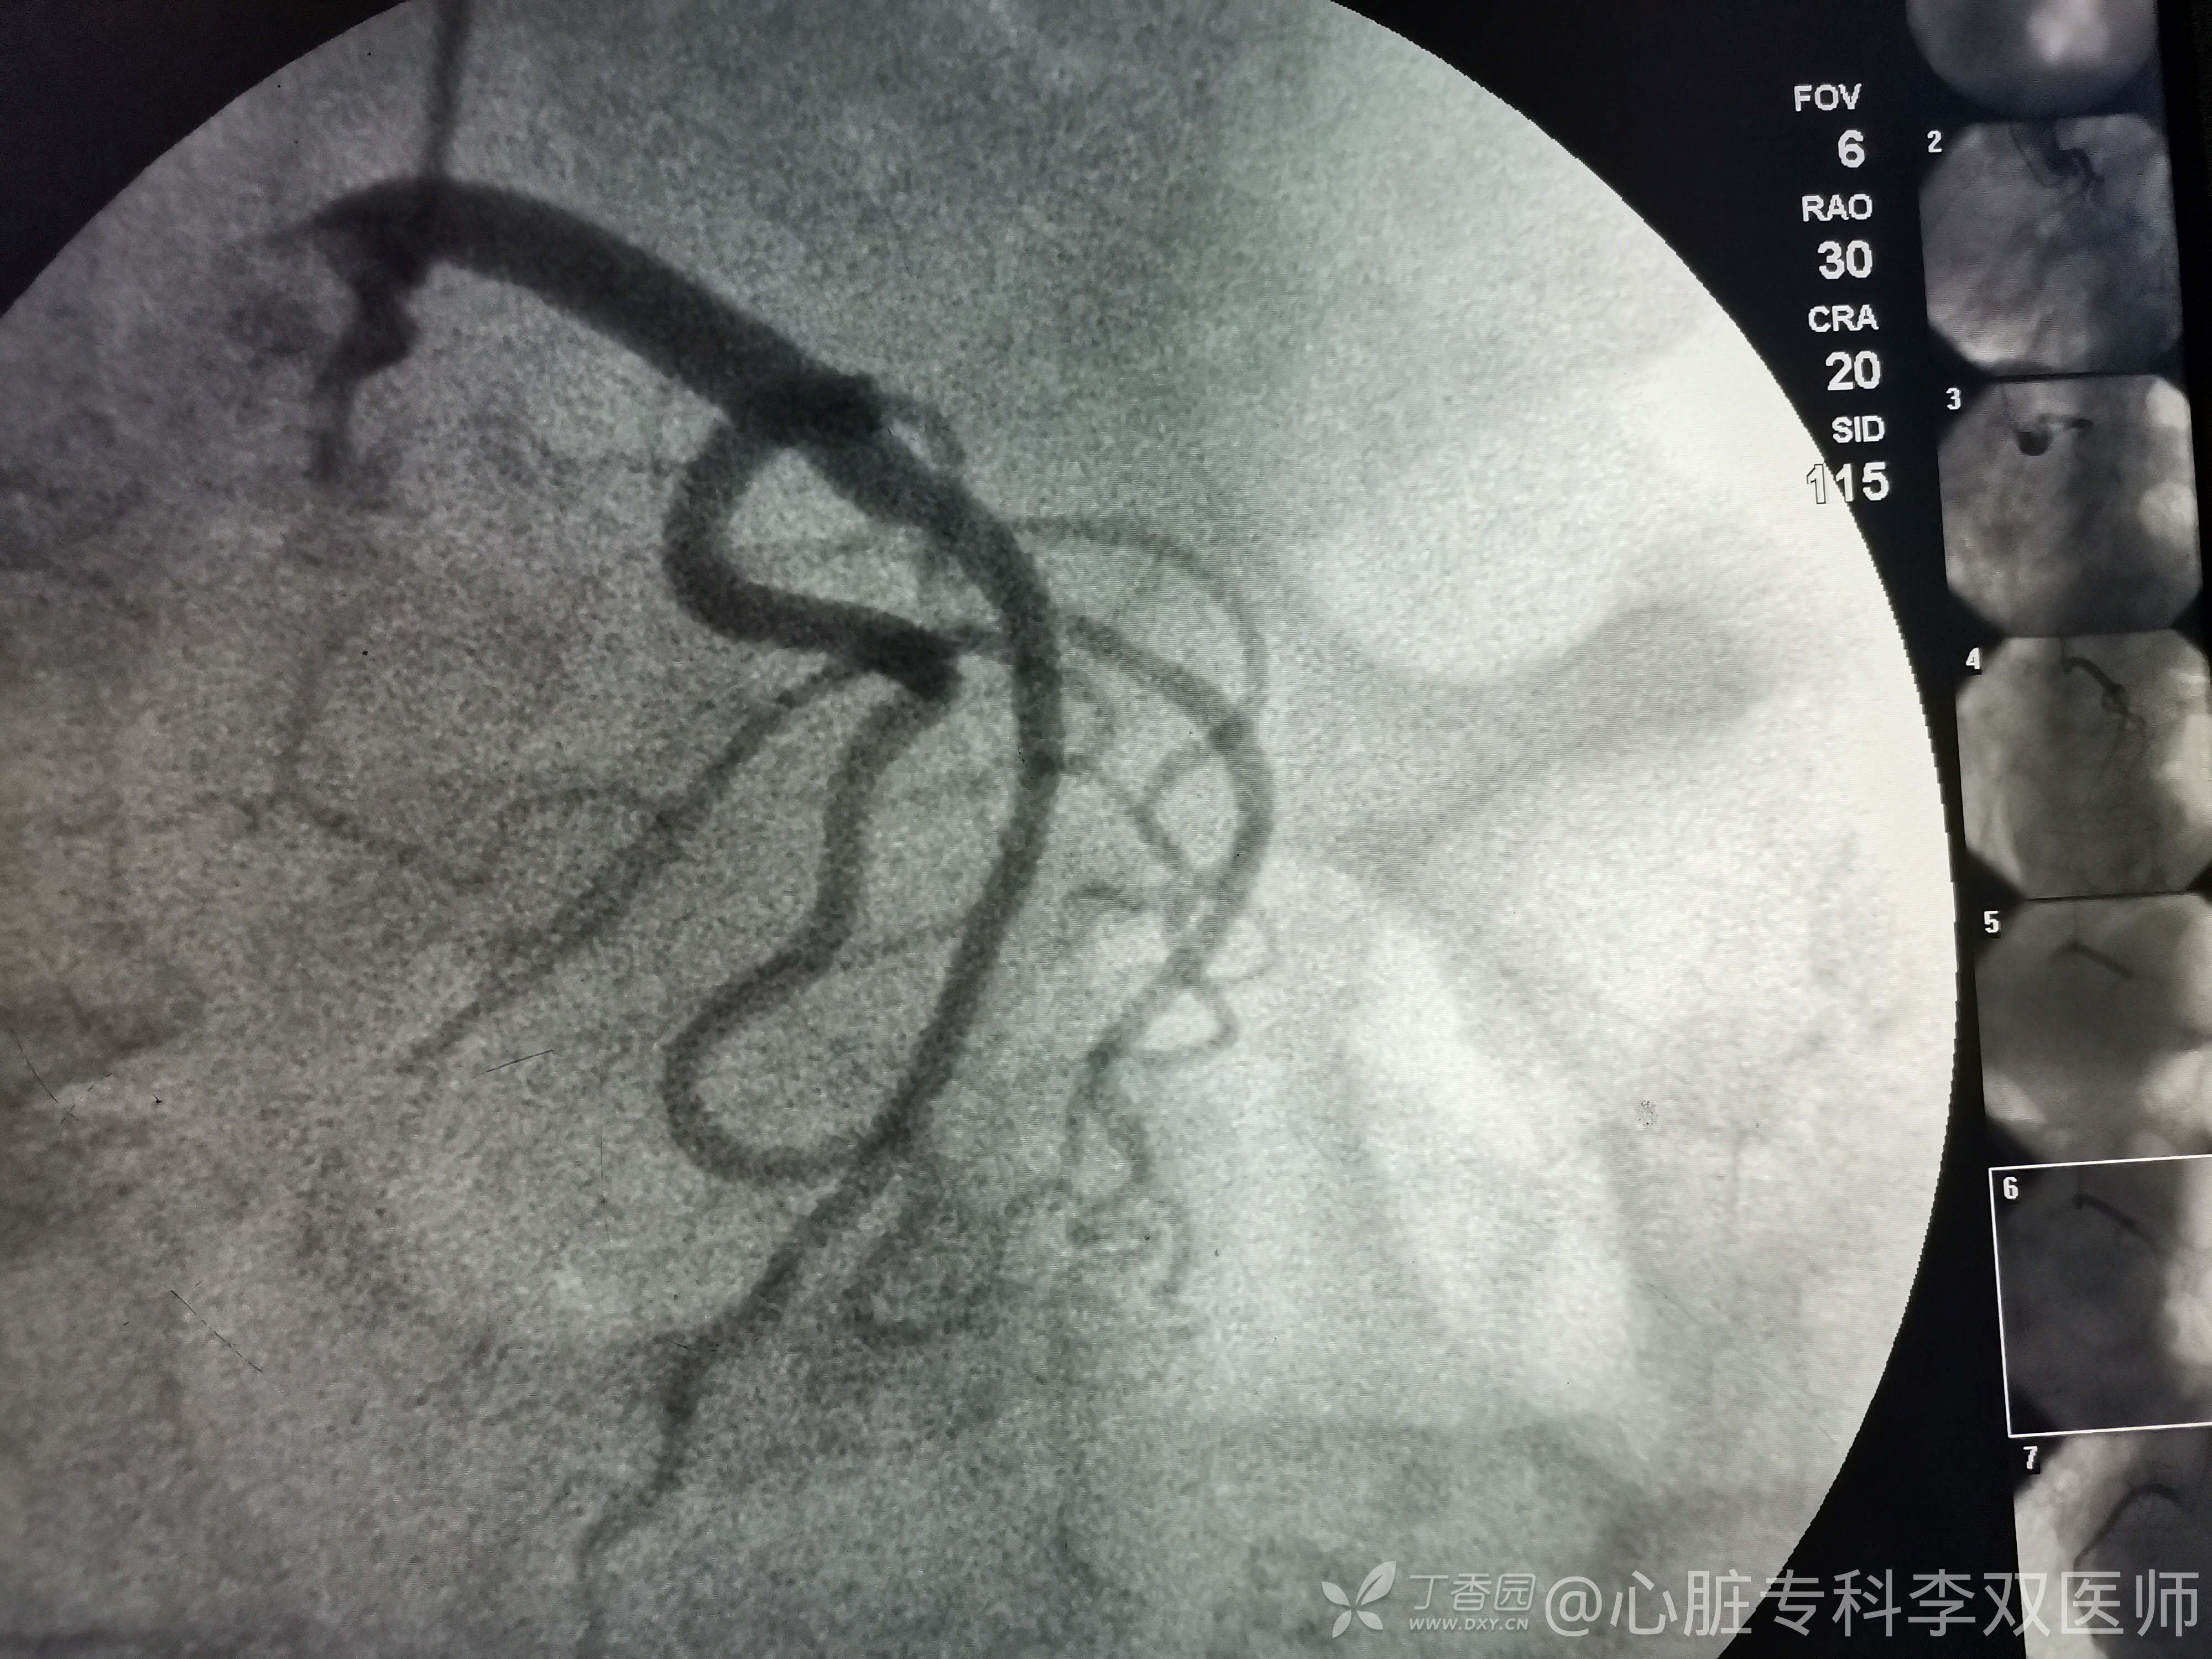

病例右位心的冠脉造影:蛮有意思的!

心血管内科医师 · 发布于 2021-07-13 · 来自 Android · IP 上海上海